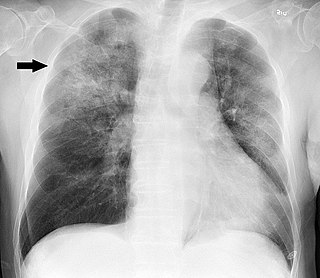

Corticosteroides en la neumonía bacteriana adquirida en la comunidad: una revisión sistemática, metanálisis por pares y dosis-respuesta

09 mayo 2023

La evidencia de certeza moderada indica que los corticosteroides reducen la mortalidad en pacientes con neumonía bacteriana adquirida en la comunidad más grave, la necesidad de ventilación mecánica invasiva y el ingreso en la Unidad de Cuidados Intensivos. J Gen Intern Med 19 de abril de 2023